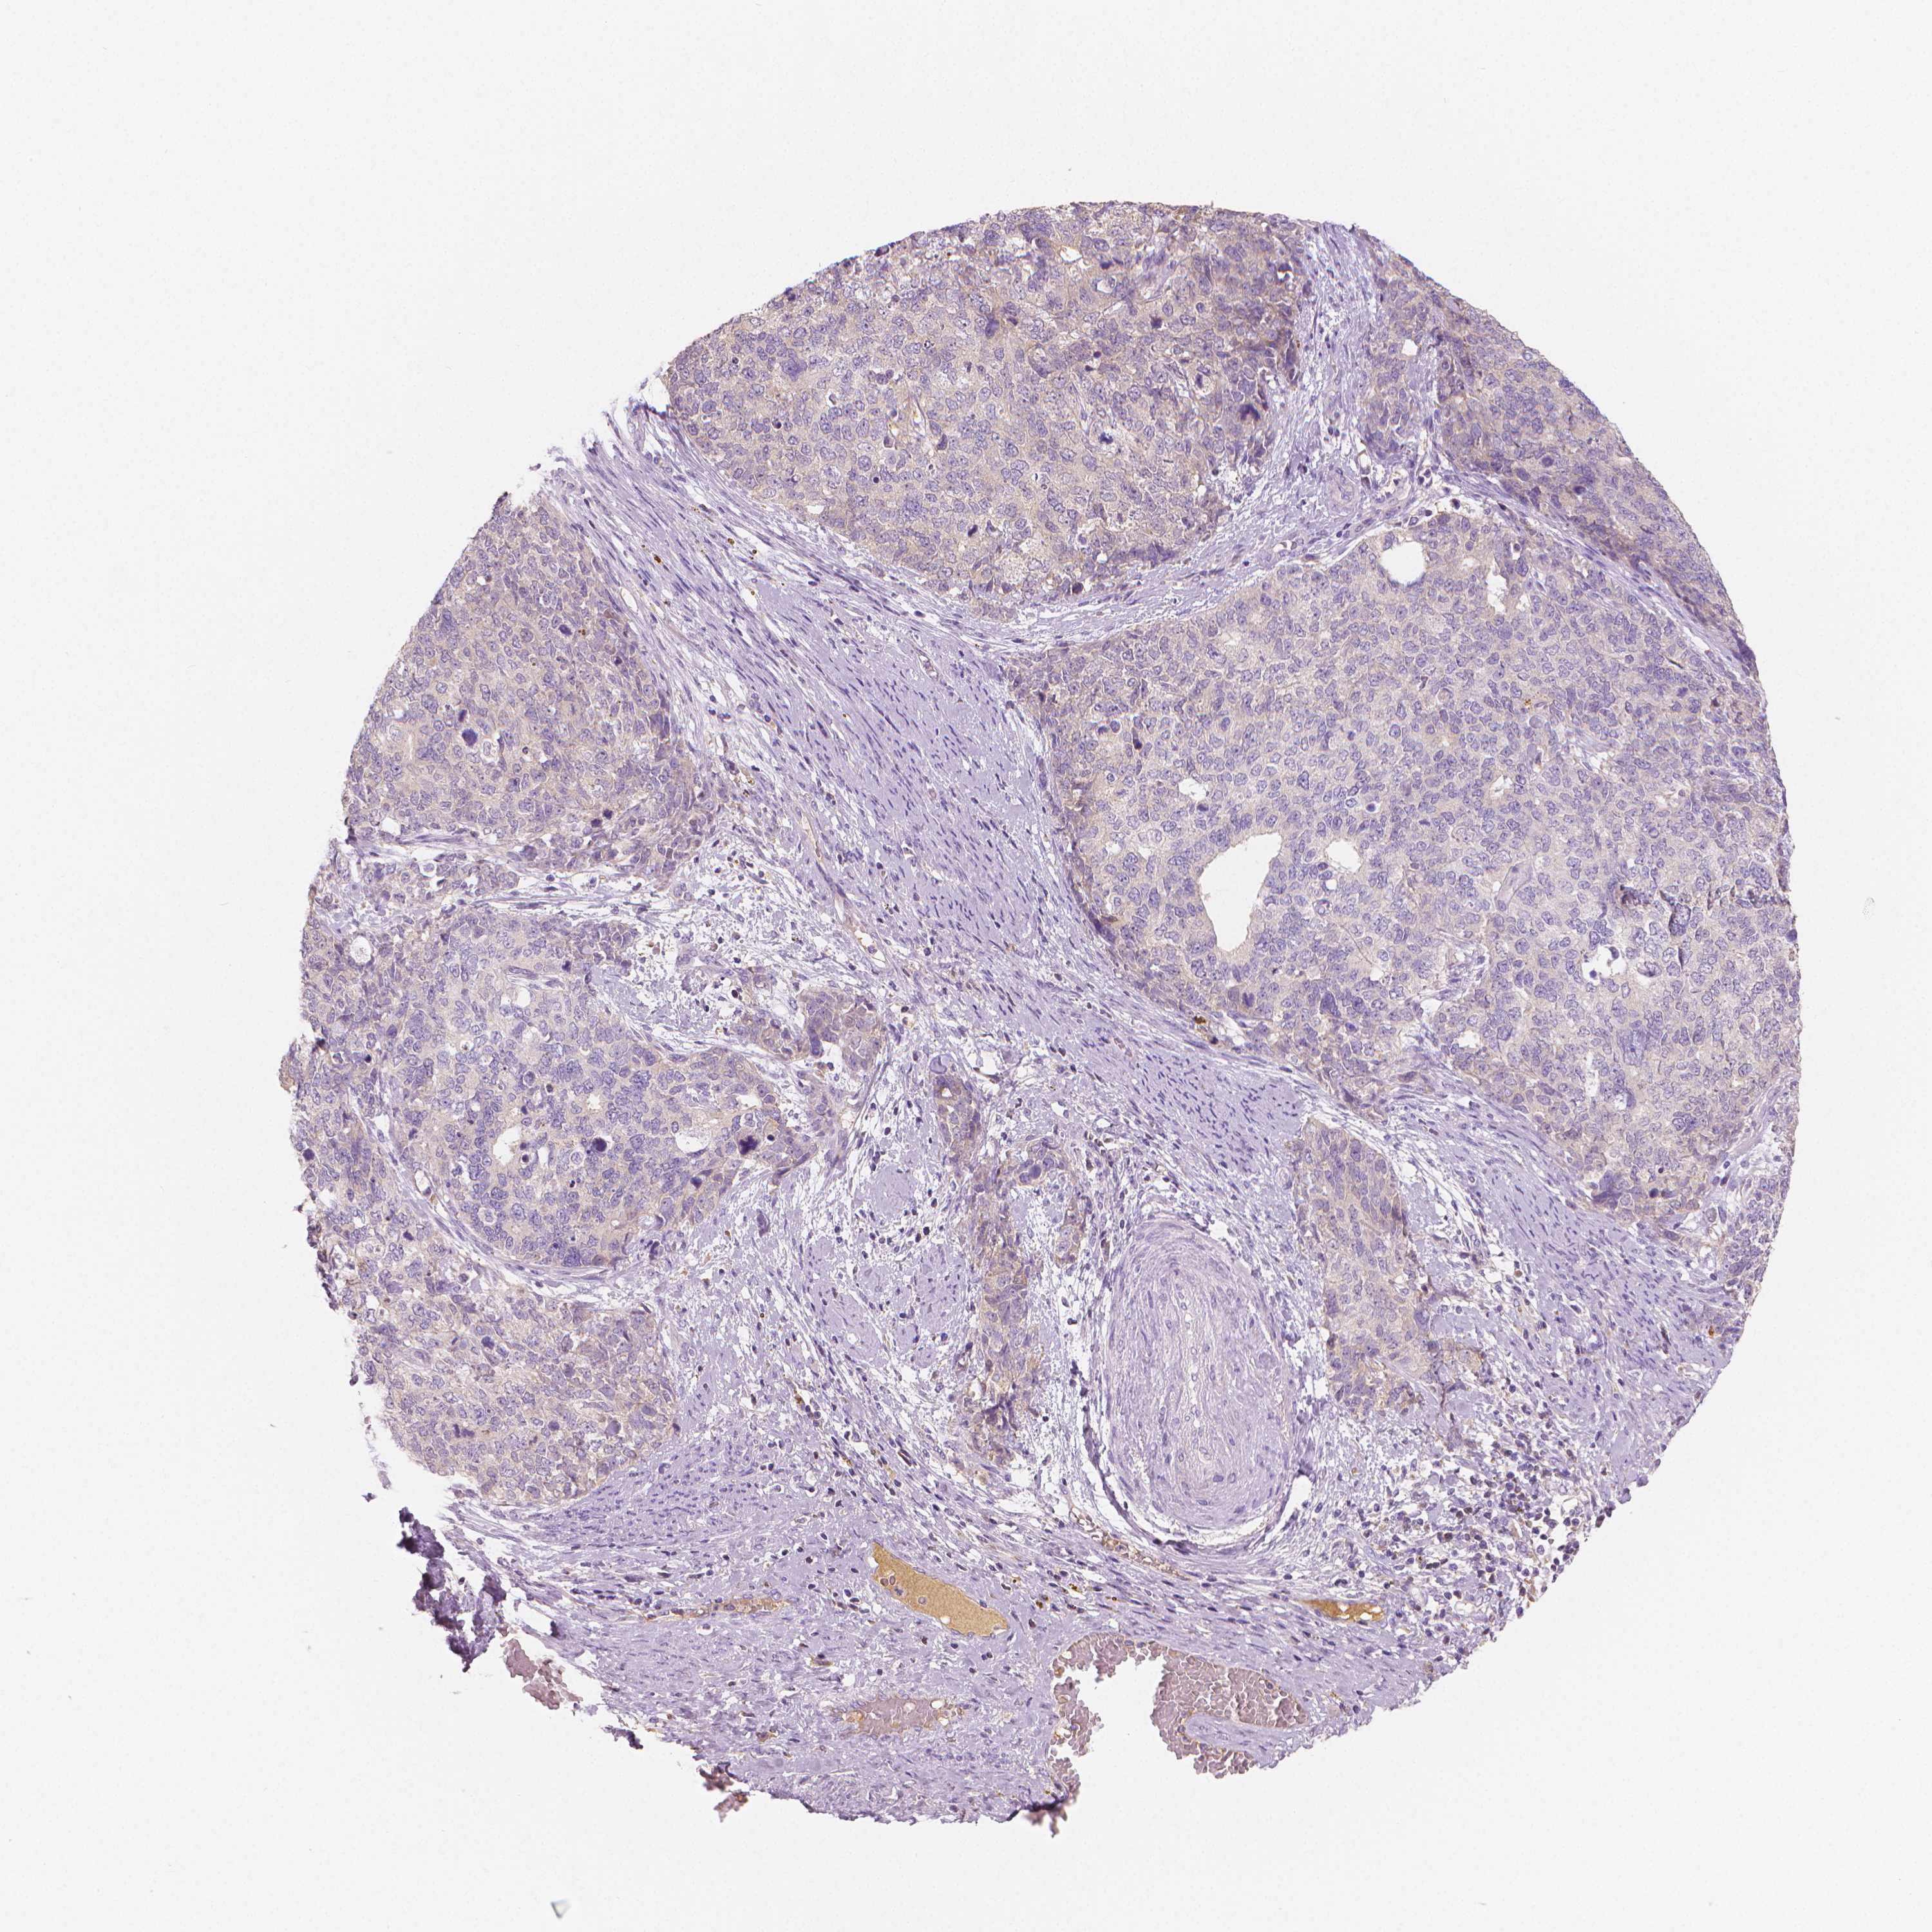

CERVICAL CANCER - Protein expressioni

A mouse-over function shows sample information and annotation data. Click on an image to view it in a full screen mode. Samples can be filtered based on level of antibody staining by selecting one or several of the following categories: high, medium, low and not detected. The assay and annotation is described here.

Note that samples used for immunohistochemistry by the Human Protein Atlas do not correspond to samples in the TCGA dataset.

Antibody stainingi

Antibody staining in the annotated cell types in the current human tissue is reported as not detected, low, medium, or high, based on conventional immunohistochemistry profiling in selected tissues. This score is based on the combination of the staining intensity and fraction of stained cells.

Each image is clickable and will lead to virtual microscopy that enables deeper exploration of all samples and also displays staining intensity scores, fraction scores and subcellular localization as well as patient and tissue information for each sample.

HPA002549

Squamous cell carcinoma, NOS

Adenocarcinoma, NOS